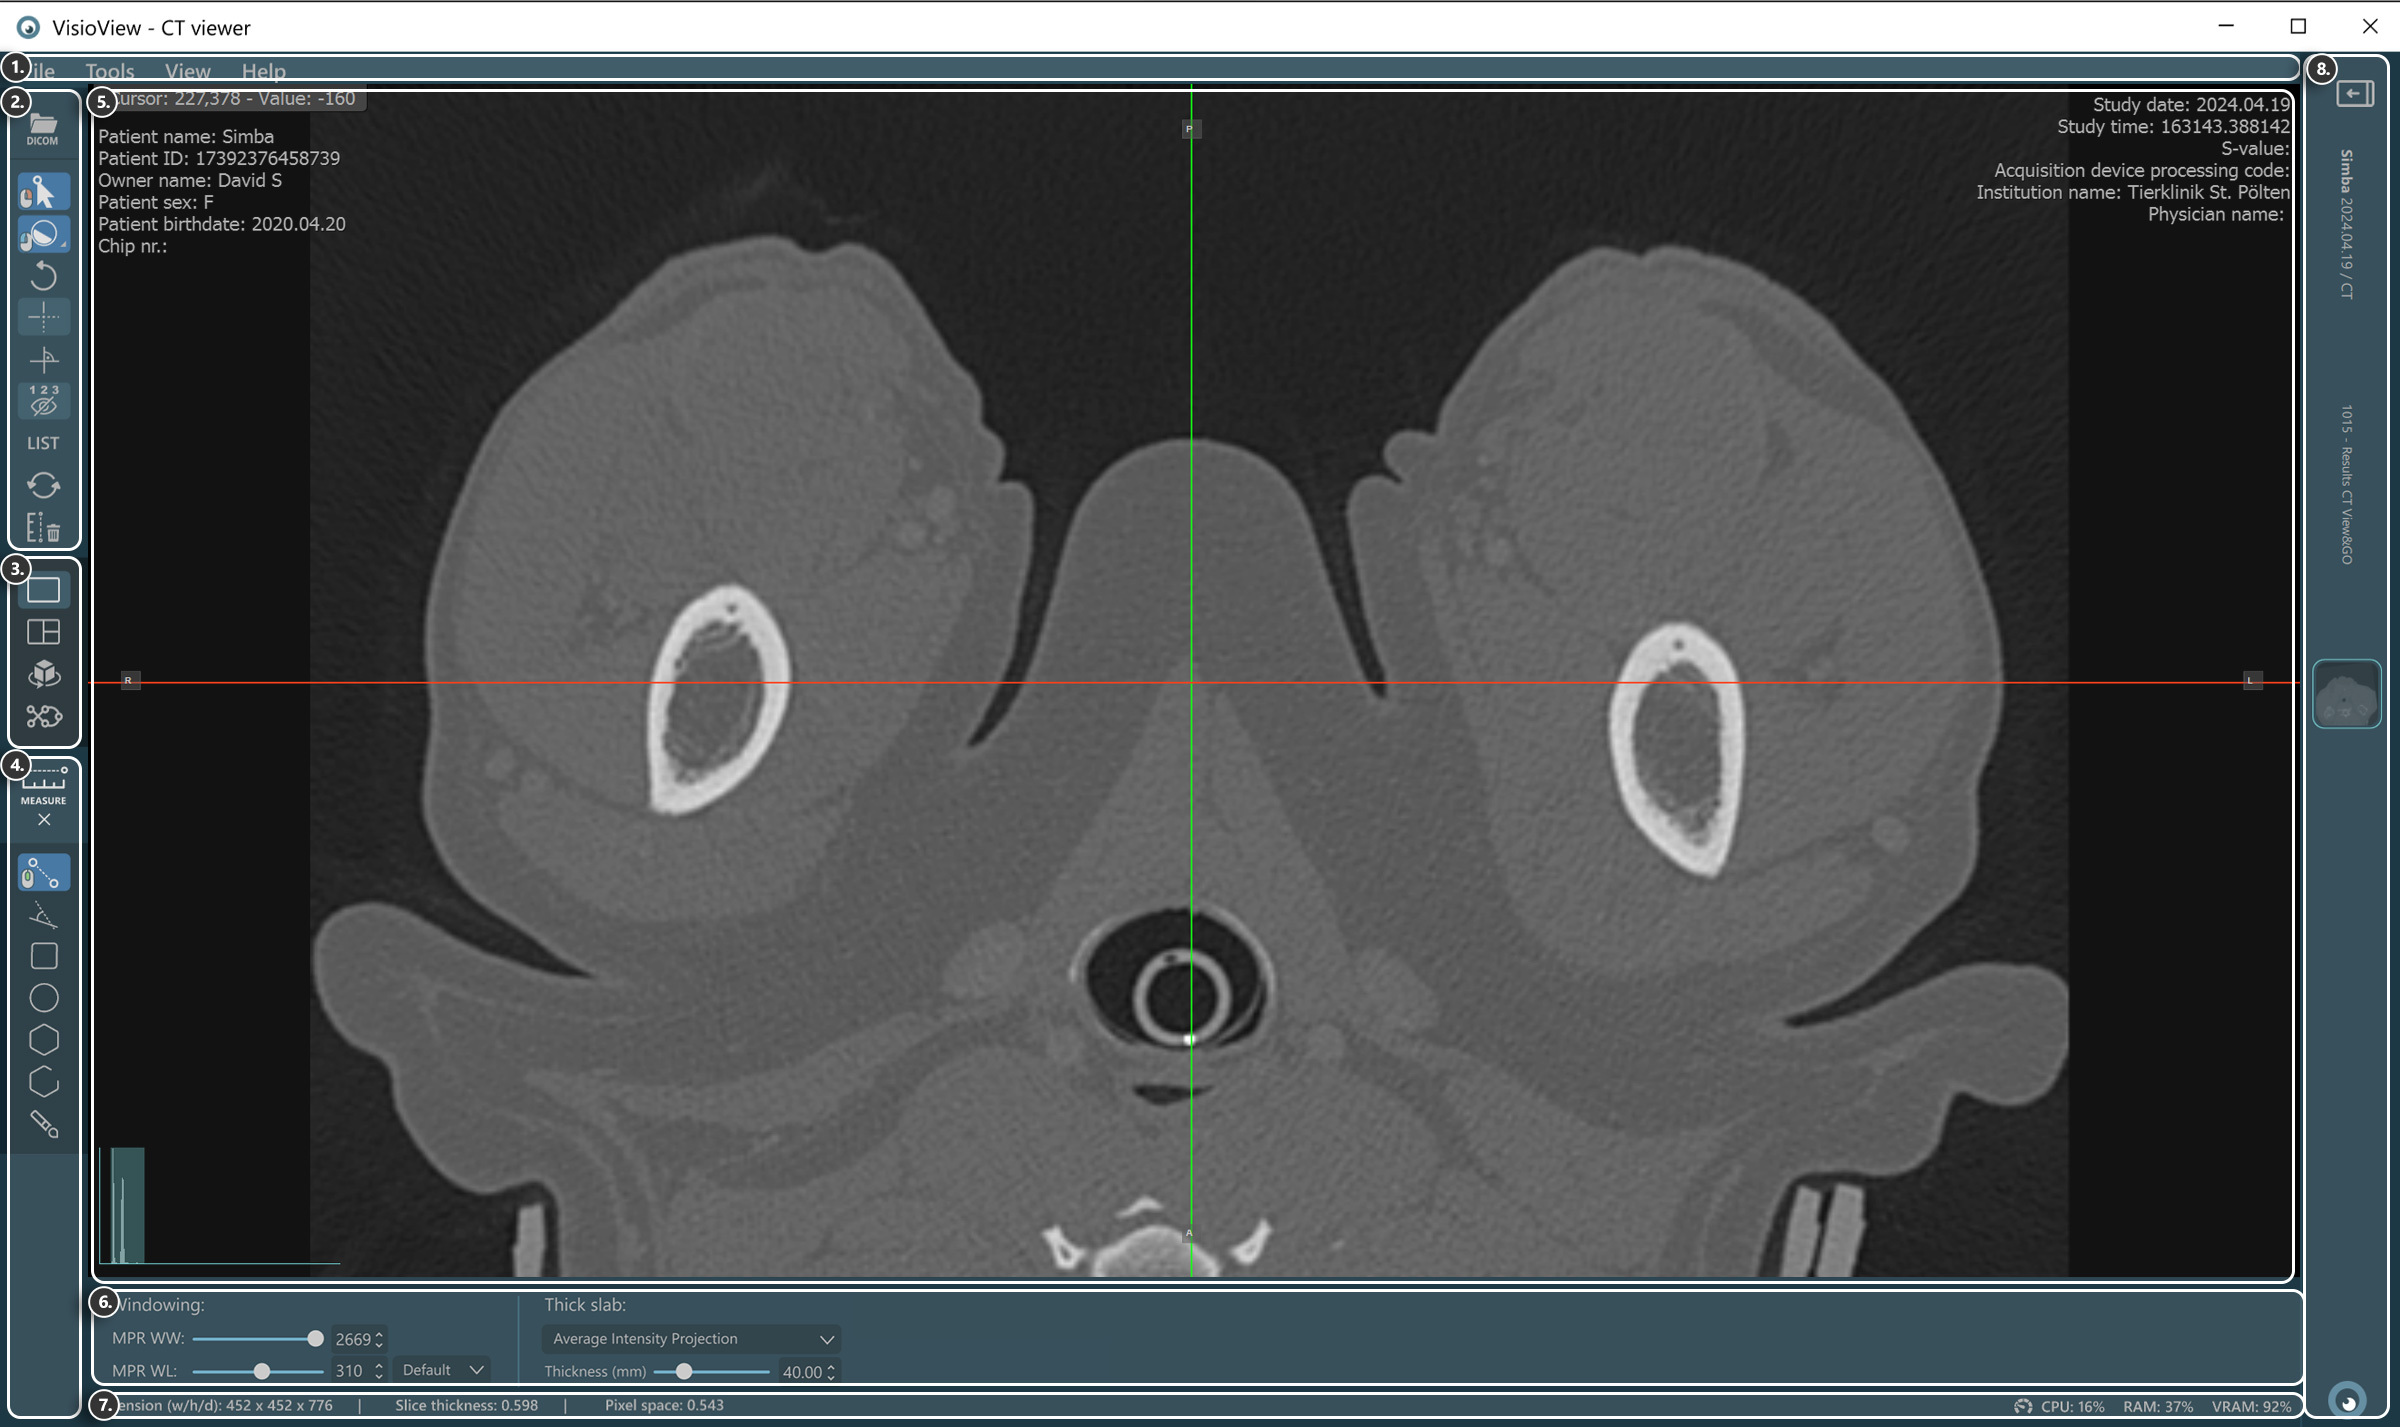

Sections of the VisioVIEW CT Viewer¶

The VisioVIEW CT Viewer consists of several sections, each tailored to a specific purpose. Below is a detailed description of each section.

VisioVIEW - CT Viewer¶

View Selector¶

Measurement Tools¶

Viewer Area¶

View Settings and Options¶

Windowing settings

Thick slab settings

Information Bar¶

DICOM image and resolution information

Performance and resource usage information